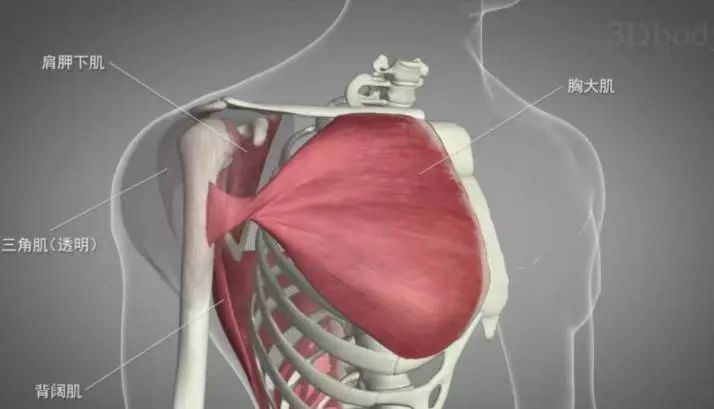

在比赛中,弯曲的肘部置于桌上,两位对手面对面,双手紧握,每位参与者都试图将对方的手压向桌面。此时,肩部的内旋肌(胸大肌、肩胛下肌、大圆肌、背阔肌等)会对肱骨近端施加一种内旋的扭力,而对手施加在手部的力则通过前臂作用于肱骨远端,形成外旋的扭力。